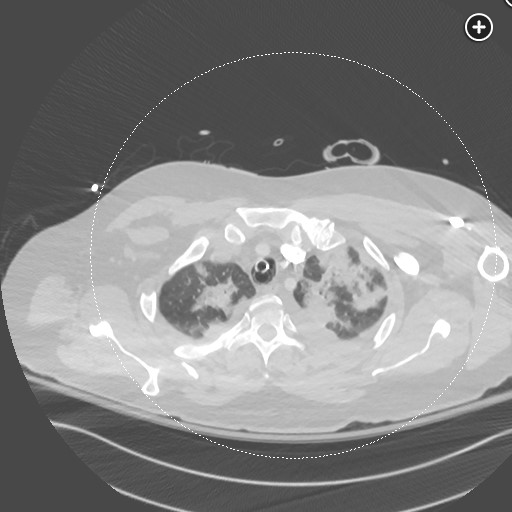

DAH CT finding includes consolidation or ground glass opacities related: DAH diffuse alveolar hemorrhage tags: #literature #pulmonology ground glass: consolidations: 1 Links to this note DAH diffuse alveolar hemorrhage DAH CT finding includes consolidation or ground glass opacities Footnotes SEEK Questionnaires ↩